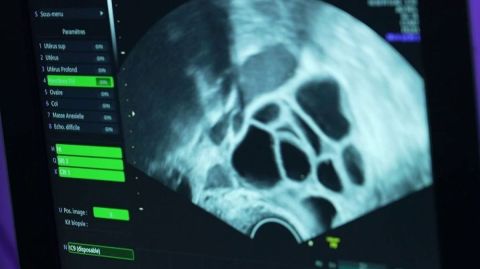

Lors des opérations de ponction d'ovocytes, les médecins enchaînent les procédures pour répondre à la demande urgente. La gynécologue obstétricienne, le Pr Noémie Ranisavljevic, décrit le processus : "Chaque bille noire sur l'écran est un follicule, renfermant un ovule qui a été stimulé." Face à l'afflux croissant, l'hôpital de Montpellier a recruté 11 personnes supplémentaires, mais cela reste insuffisant face à l'explosion des demandes. "Les délais de plus de deux ans poussent malheureusement les femmes de plus de 35 ans à s'orienter vers l'étranger pour congeler leurs ovocytes," ajoute-t-elle.